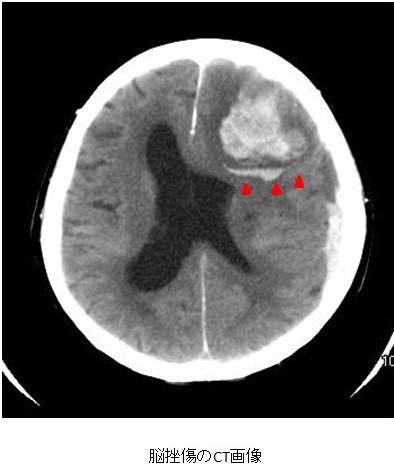

脳挫傷の診断はCTやMRIなどの画像検査で行います。挫傷した部分の脳は壊死や出血、浮腫が混在しています。CTでみると、正常の脳よりもやや黒っぽくなった部分(=浮腫や壊死)のなかに点状の白い部分(=出血)がモザイク状に散在して見えます。脳挫傷の症状は、頭痛や軽度の意識障害のようなものから、麻痺、言語障害、失語症、意識障害などの重篤なものまで、損傷の部位と大きさにより様々です。脳挫傷に伴う進行性の出血や脳浮腫が増大することで症状が悪化することがあります。